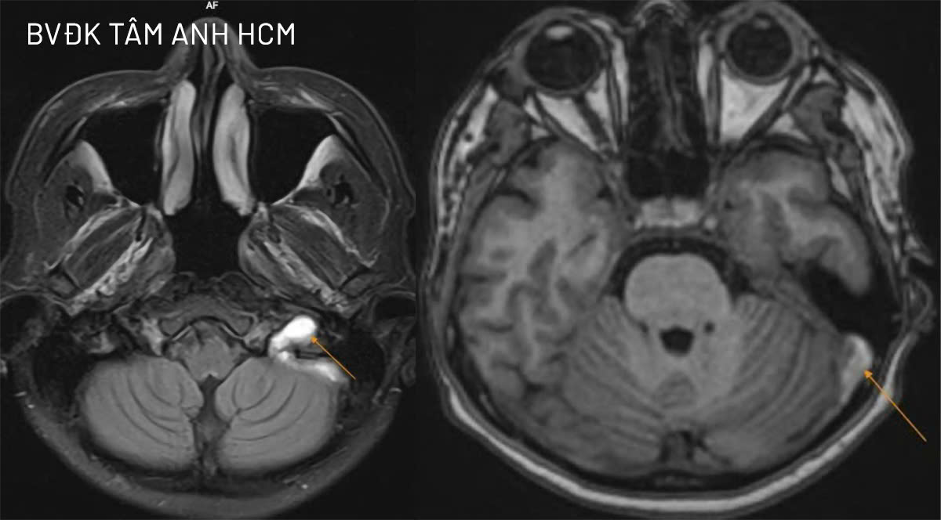

Doctor Cao Hoang Trong, from the Department of Neurology, Neuroscience Center, Tam Anh General Hospital Ho Chi Minh City, stated that Mai was conscious, had no slurred speech, no limb weakness, and no seizures. A 3 Tesla MRI scan of the patient's brain blood vessels revealed a blood clot in the left internal jugular vein, obstructing blood flow at the jugular foramen segment. The clot was in the subacute phase and had spread to the sigmoid sinus and a portion of the left transverse sinus.

MRI image shows the blood clot almost completely blocking the left internal jugular vein, spreading to adjacent venous sinuses. *Tam Anh General Hospital*. |